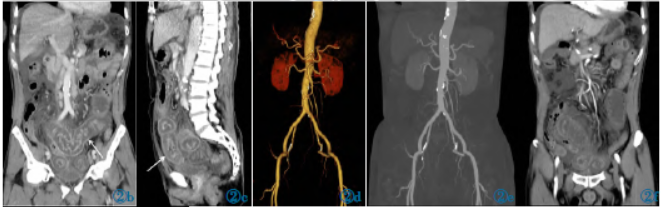

CT平扫、增强表现:平扫显示胃幽门管、多处小肠壁呈节段性环形增厚,管腔变窄,以小肠为著,最厚处管径约为4.6cm、肠壁约为1.7cm,肠壁密度降低CT值约为18HU,肠腔内积液CT值约为16HU;受累肠壁浆膜面模糊不清,所属肠系膜、网膜脂肪间隙显示模糊,呈片絮状改变;肠系膜区及腹膜后、肝胃间隙多个淋巴结显示,腹盆腔积液(图1)。

图1AAPCT平扫表现。图1a:腹部平扫CT横断位显示胃幽门管增厚(实线箭头所指),密度降低,管腔变窄,浆膜面模糊;肝周间隙积液(虚线箭头所指)。图1b,1c:显示多处小肠壁呈节段性环形肿胀、增厚(箭头所指),肠壁密度降低,肠管横断位呈“双线征”(图1c),肠腔变窄、积液,浆膜面模糊不清,肠周渗出、积液改变。